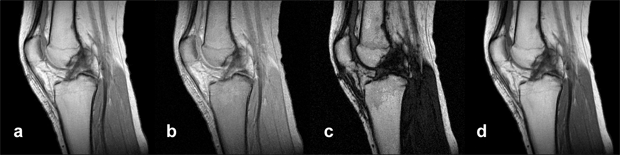

Figure 15-09a:

Simulation of an MR exa­mi­na­tion of a normal knee at 1.5 T. Series of synthetic inversion-recovery ima­ges; parameters TR|TE|TI: (a) 1000|10|20; (b) 1000|10|100; (c) 1000|10|260; (d) 1000|10|500.

Simulation software: MR Image Expert®